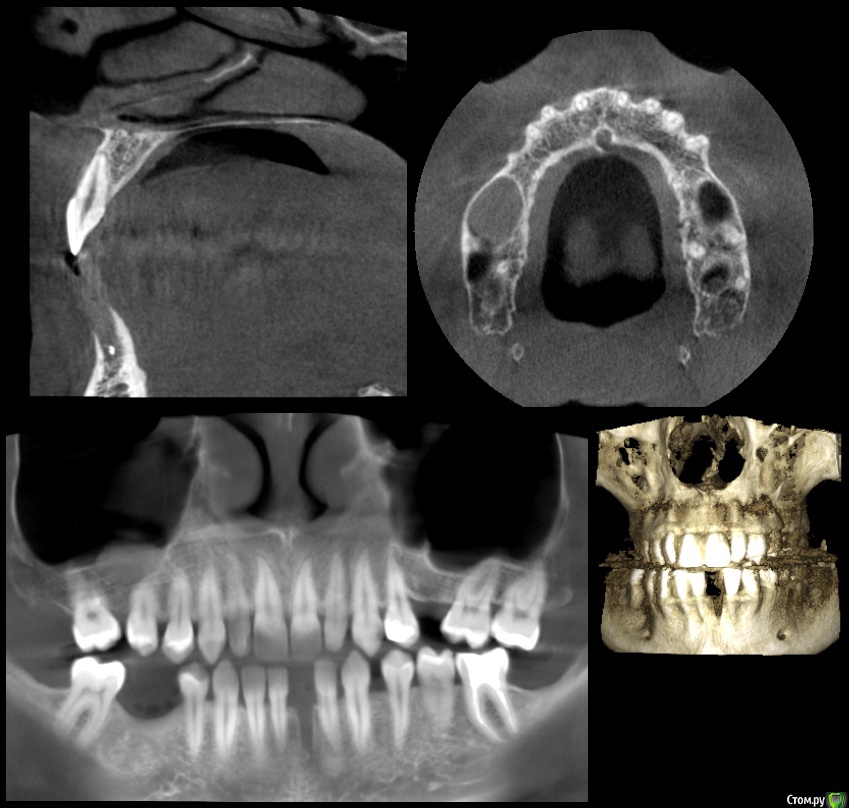

nemorr Опубликовано 14 сентября, 2020 Поделиться Опубликовано 14 сентября, 2020 Кт зубовhttps://yadi.sk/d/6aZXi03bqS5B5Q Здравствуйте.Хотел обратиться по поводу проблем с зубами. Пред история.Началась проблема с 31 зуба в марте этого месяца.Был пульпит, пролечили. Но спустя 2 недели он заболел вновь. На снимках выглядел хорошо, я долго терпел он не прошел, приняли решение очистить, канал был один. Заложили уже йодекс на подольше. Зуб в итоге прошел через 1.5 месяца должен был его долечить, но ковид испротил все планы. Провалялся в больнице, месяц потом ещё месяц болел дома. В августе зуб опять заныл, поменял лекарство на кальсепт стало ещё больнее, на 3d виден выход кальсепта за верхушку корня, не большое потемнение под корнем, возможно гранулёма (в марте не было) Тактик лечения было несколько. 1)Так как есть проблемы с прикусом и суставом. 2) После каждого лечения 31 зуб сдвигался немного и мешал жевать (его потом чуть чуть подпиливали)Было предположение что я настукиваю прикусом зуб и он из-за этого не проходит. В очередной раз почти вывели его из прикуса, нажимать я на него перестал, но боль не прошла. В итоге его открыли так как при попытки сменить лекарство ещё раз при чистом канале эскудат выступил видимо из под корня зуба. Решили оставить открытым полоскать. Боль после этого реально прошла! Неделю я радовался как ребенок и собирался уже идти закрывать зуб обратно. Но уехал за город там видимо подмерз зуб разболелся с новой силой, я плюнул на всё и его удалил. Под зубом была не большая гранулёма. Через 3-5 дней боль снизу ушла.Это всё была пред история. Через неделю у меня заболел 21 зуб. Он у меня живой не депульпированный кариеса на нем нет!. Единственное что связывает его с 31 зубом это прикус.Боль потихоньку начала нарастать. Характер боли: Сам зуб при надавливании ощущается дискомфорт, как будто что мешает. Но после того как его по шевелишь боль усиливается и сильно воспаляется боль распространяется на соседние зубы. Боль не стреляющая но может быть не только вопалительной но и жгучей. Голова конечно от этого болит. Если зуб не тревожить то боль уменьшается.Делали ЭОД 2 раза 8 и 6 мкА показало. Ссылка на комментарий

nemorr Опубликовано 17 сентября, 2020 Автор Поделиться Опубликовано 17 сентября, 2020 А что нибудь пояснить?Лекарство в лунке 31 у меня какое-то временное. Или каласепт или йодекс. Врачи говорят что само в растворится.По поводу кисты/полипа в правой пазухе. У меня хронический насморк давно. Чуть меньше года назад была в левой большая, а в правой минимум. ЛОР хирург сказал что если нормально дышишь лучше не удалять, а применять терапевтическое лечение. Что я и делал, тафен назаль. Сейчас вот картина обратная выросла справа, а слева уменьшилась. Но болит именно 21 зуб который сверху слева. Боли уже напоминают невралгию. Невролог прописал фенлипсин пью. Но невролог сказал зуб всё равно депульпировать. Понажимал на лицо сказал на истинную невралгию не похоже, пишет невралгия из-за зуба.Но стоматологи не видят проблемы в 21 зубе не какой. Ссылка на комментарий